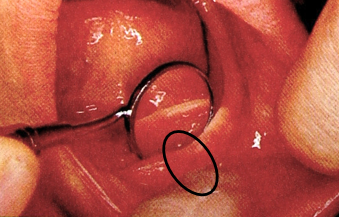

4.舌系带(lingual frenum)

连接口底与舌腹的粘膜皱襞,位于口底中线部,活动度较大。

取印模时应嘱患者将舌向后上方,取功能状态印模。

基托此处作切迹利于固位。